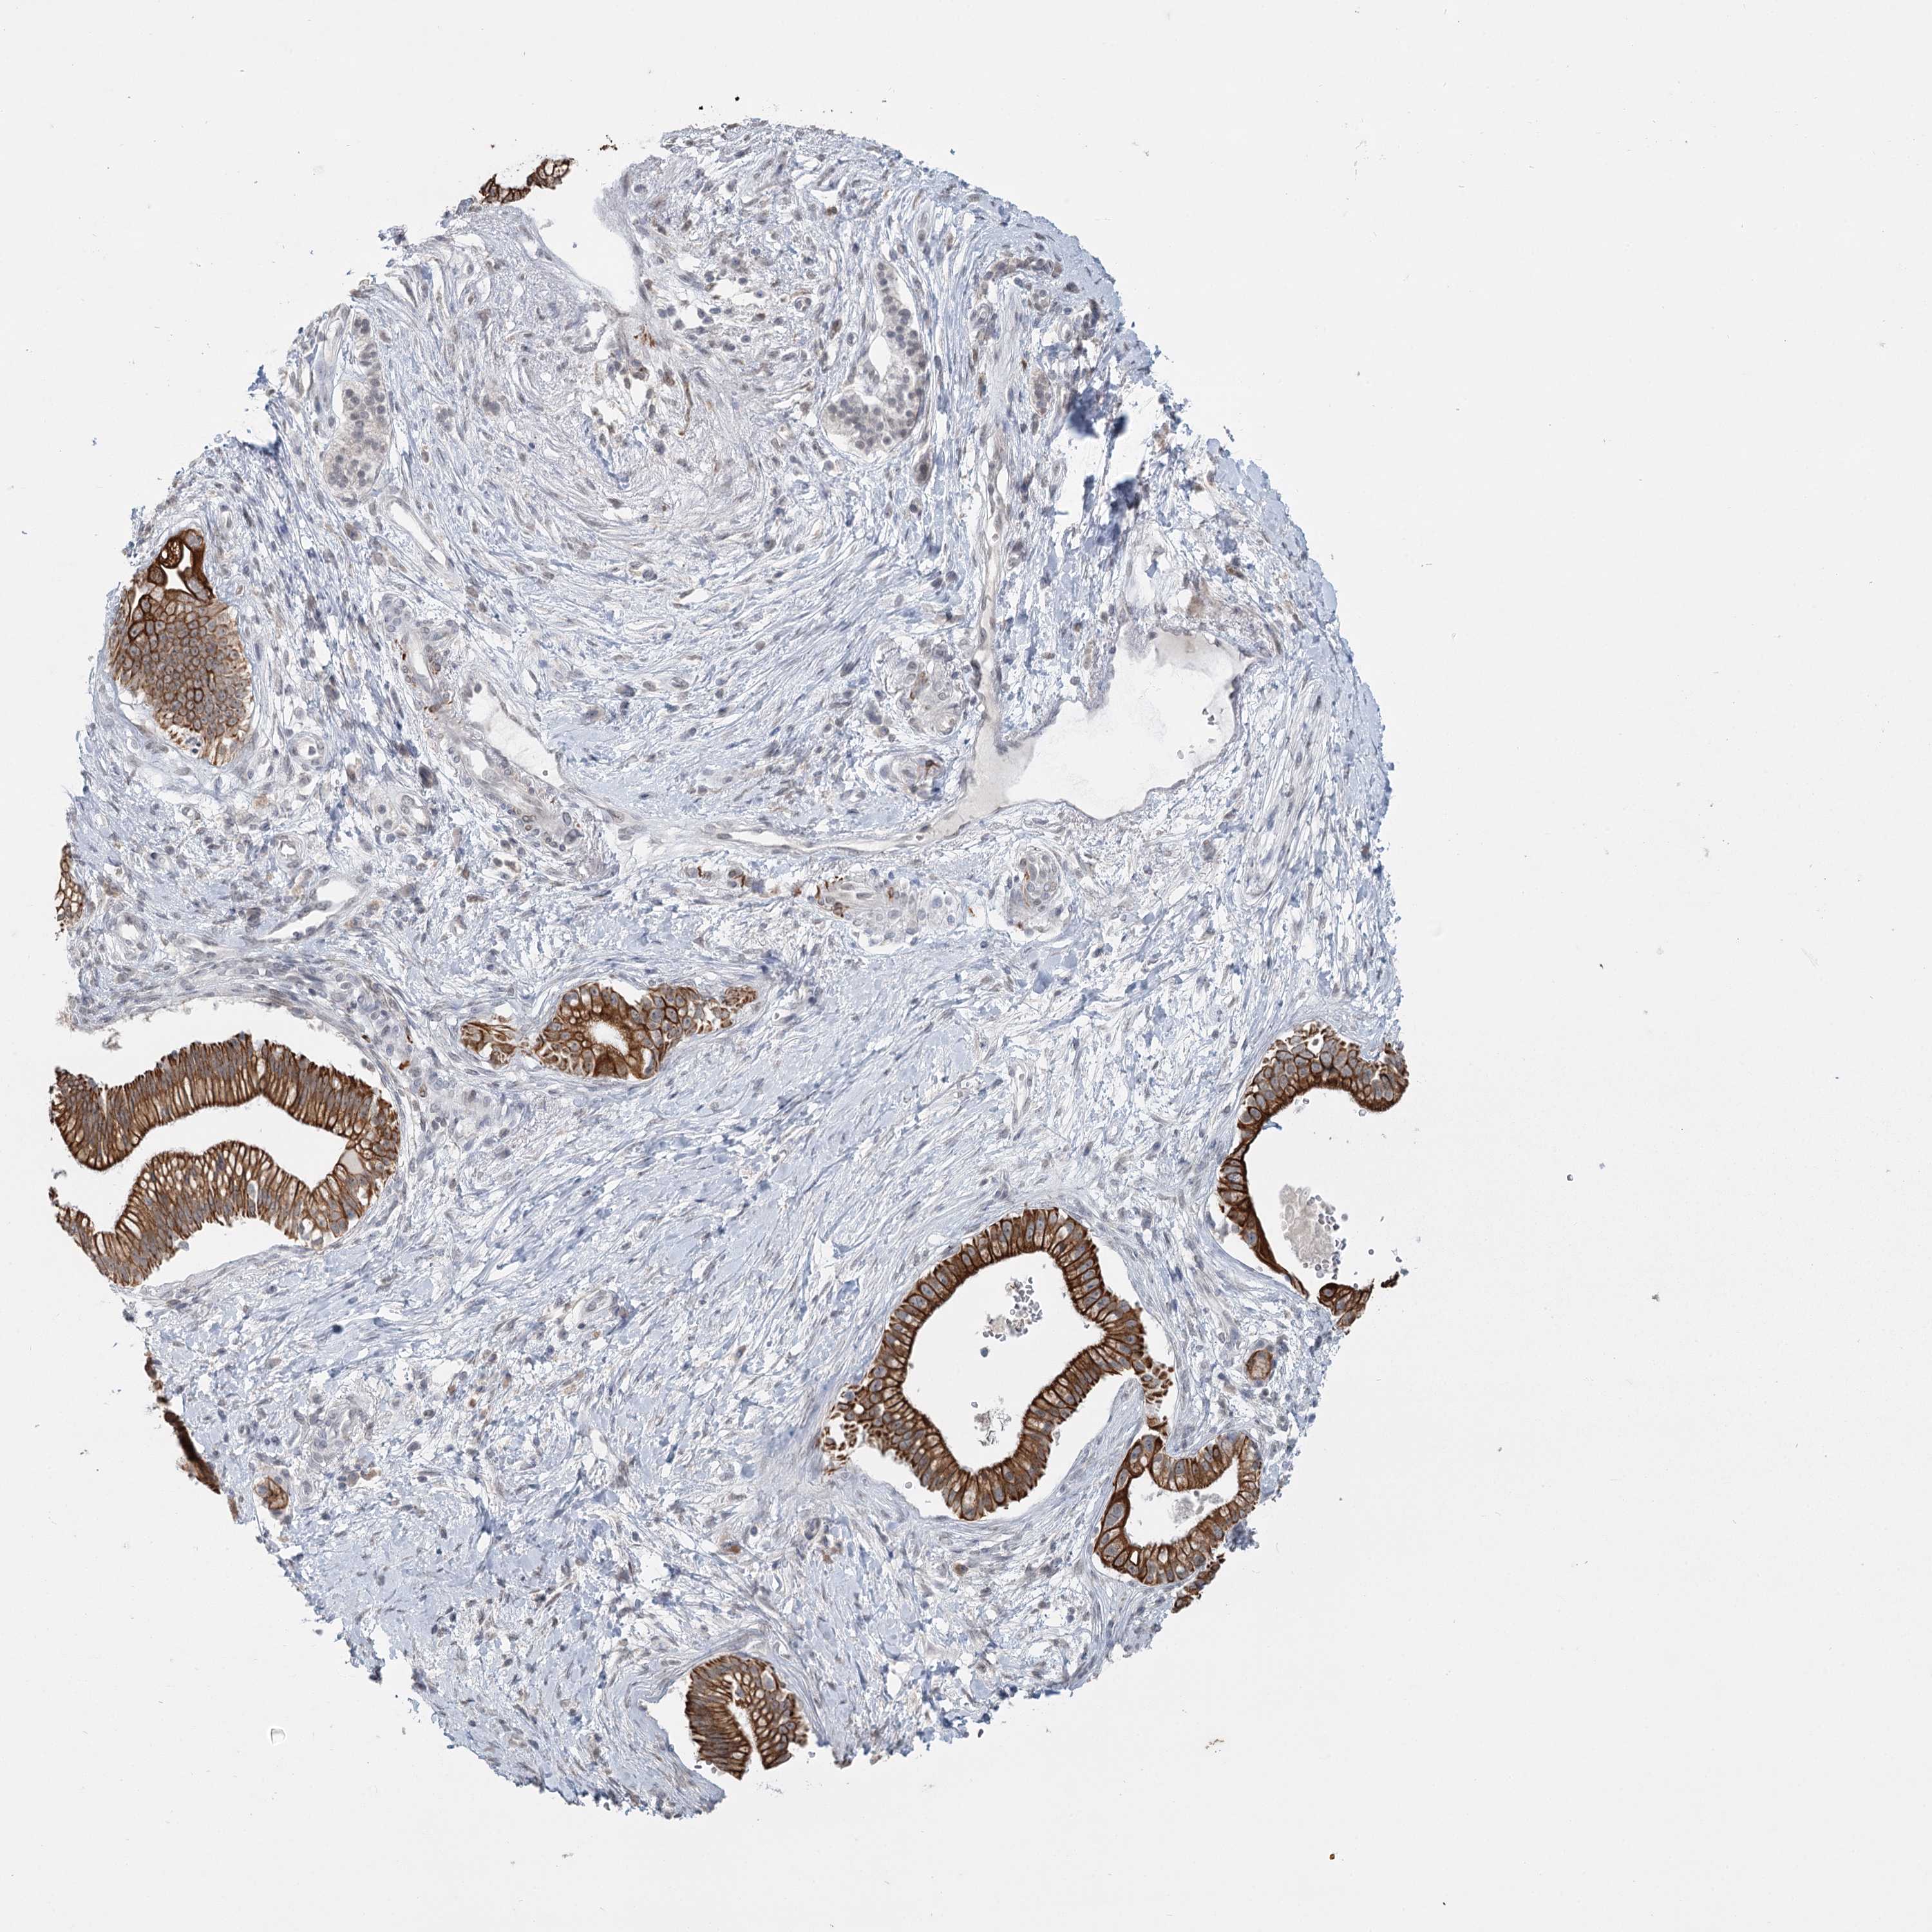

PANCREATIC CANCER - Protein expressioni

A mouse-over function shows sample information and annotation data. Click on an image to view it in a full screen mode. Samples can be filtered based on level of antibody staining by selecting one or several of the following categories: high, medium, low and not detected. The assay and annotation is described here.

Note that samples used for immunohistochemistry by the Human Protein Atlas do not correspond to samples in the TCGA dataset.

Antibody stainingi

Antibody staining in the annotated cell types in the current human tissue is reported as not detected, low, medium, or high, based on conventional immunohistochemistry profiling in selected tissues. This score is based on the combination of the staining intensity and fraction of stained cells.

Each image is clickable and will lead to virtual microscopy that enables deeper exploration of all samples and also displays staining intensity scores, fraction scores and subcellular localization as well as patient and tissue information for each sample.

Antibody HPA023187

Antibody CAB034226

Staining

High

Medium

Low

Not detected

Intensity

Strong

Moderate

Weak

Negative

Quantity

>75%

75%-25%

<25%

None

Location

Nuclear

Cytoplasmic/membranous

Cytoplasmic/membranous,nuclear

Adenocarcinoma, NOS